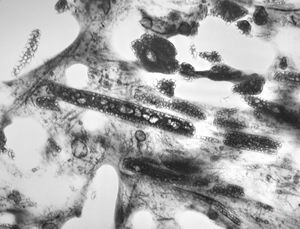

F,25y. | giant multinuclear osteoclast - aneurysmatic cyst - tibia

M,67y. | pseudogout - pyrophoshate arthropathy